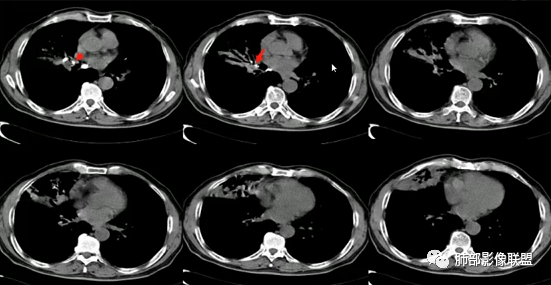

上图,鳞癌,腔内软组织占位,局部膨大,不均匀强化,伴远端粘液栓。

上图,小细胞肺癌,病灶从肺门朝外沿支气管爬行,呈指套样改变,病灶周围阻塞性肺炎较轻。

上图,粘液表皮样癌,支气管腔内病灶轻中度强化。

上图,类癌,支气管腔内占位,强化明显,远端粘液栓。

上图,支气管结石(红箭头),远端阻塞性炎症,腔内粘液栓。